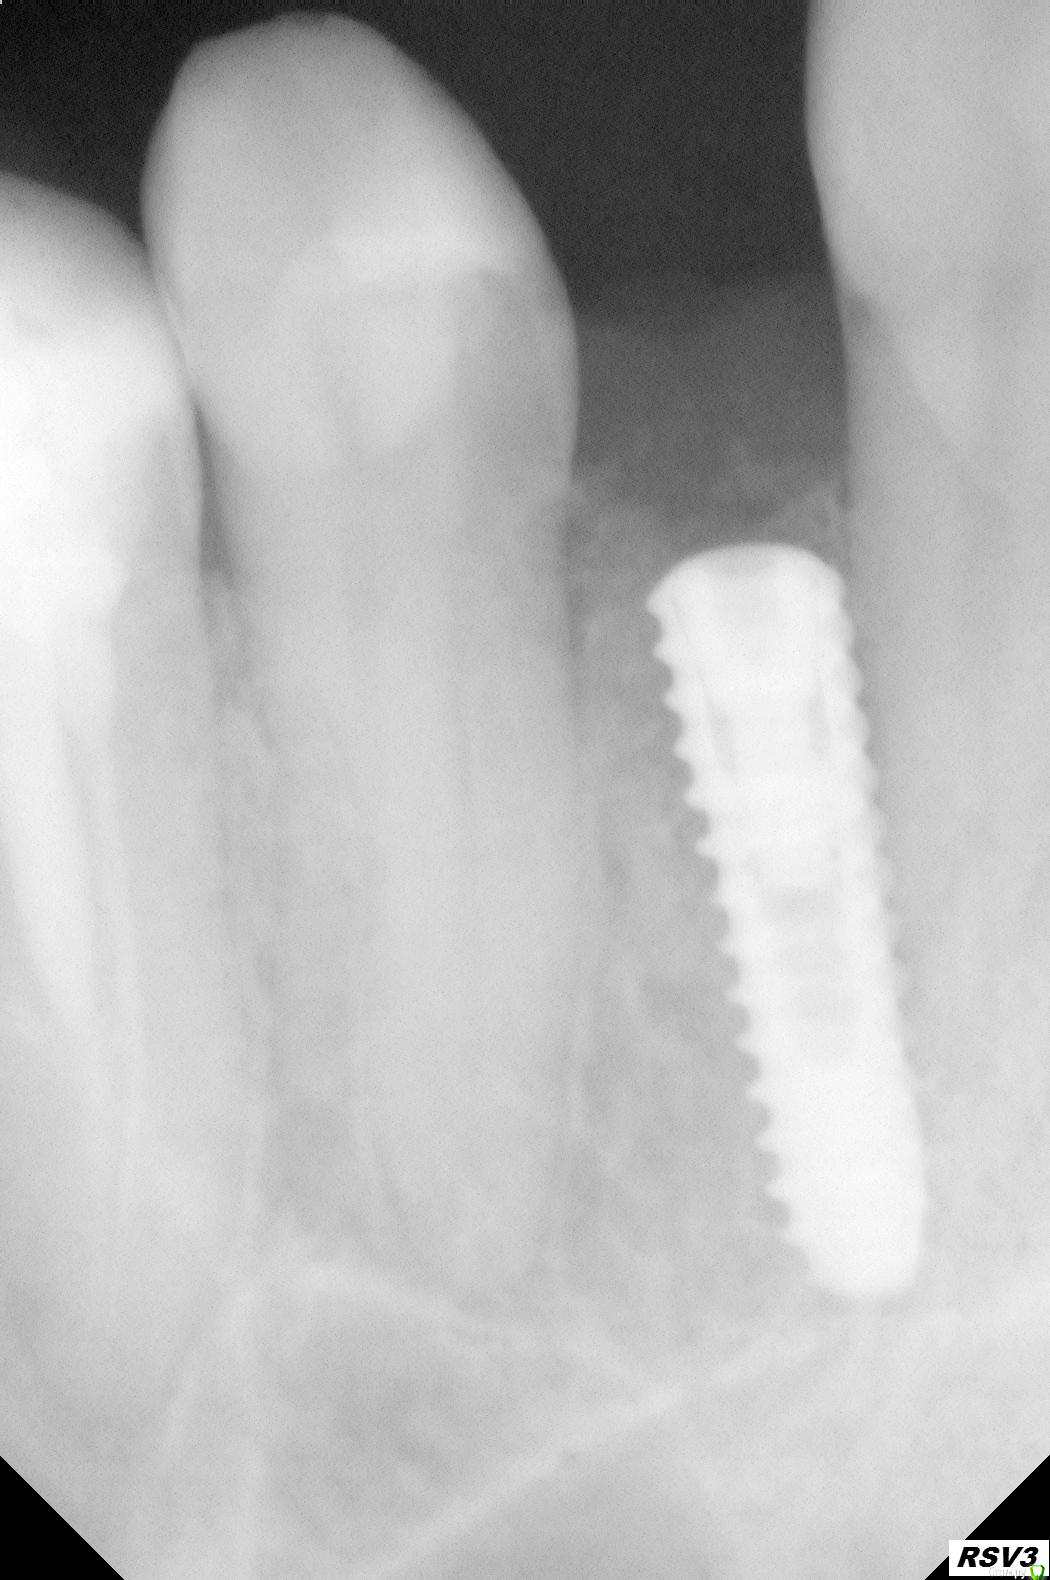

Godunov Опубликовано 29 октября, 2014 Поделиться Опубликовано 29 октября, 2014 Добрый день!Имплант вкручен 3 месяца назад, походил с расширителем и когда мой врач сделала снимки, то задумалась.Мой лечащий врач стоматолог, сначала остановилась на решении что надо выкручивать и вкручивать с учетом угла корней. Мне не хотелось (риск что имплант может неприжиться). Убедила аргументом, что 5 зуб живой и полном расцвете сил и жалко его потерять если имплант под нагрузкой его повредит.Сейчас мне говорят что лучше оставить как есть, потому что хирург-имплантолог сказал, что при выкручивании можно повредить корни. Профи, как правильнее будет сделать? С уважением Имплант внизу,справа, между 5 и 7 зубом. Мне 46 лет.http://i004.radikal.ru/1410/64/dbb1c3924912.jpghttp://s016.radikal.ru/i335/1410/54/6c9acae821b8.jpg Ссылка на комментарий

Zborzh Опубликовано 29 октября, 2014 Поделиться Опубликовано 29 октября, 2014 Не обязательно,что Имплантат касается корня,они могут быть в разных плоскостях.сделайте КТ 3 Ссылка на комментарий

Heatshock Опубликовано 30 октября, 2014 Поделиться Опубликовано 30 октября, 2014 Соглашусь с колллегами по поводу временной коронки. Исходя из предоставленных снимков, есть вероятность, что 7ку нужно будет весьма сильно запилить. Это нужно для того чтобы адекватно проснять оттиск, создать полноценный контактный пункт и для нормальной гигиены.Временная коронка необходима на срок минимум 2 месяца, для того чтобы создать правильный десневой контур, проверить полноценность контактных пунктов с соседними зубами, проверить гигиену (не происходит ли застревание пищи между 6 и 7 зубом) ну и посмотрите, как реагирует 5ка. Тем не менее я бы рекомендовал сделать КТ этой области. А постоянную работу нужно будет выполнять на индивидуальном абатменте.Ниже примерный контур коронки: http://nyazo.jp/6__6WcgJ.png 3 Ссылка на комментарий